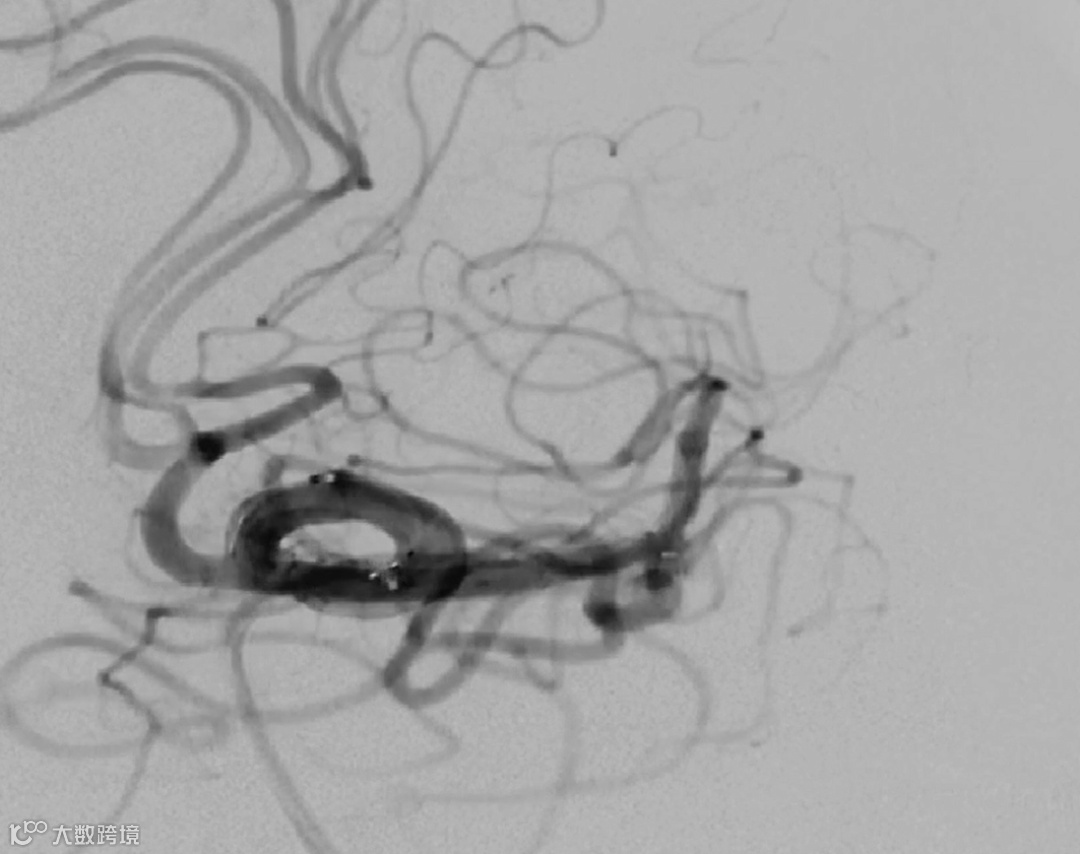

全部释放完成后,造影显示,分支血管及载瘤动脉血流通畅。

解脱后,多角度复查造影,可见动脉瘤瘤腔内有明显造影剂滞留,分支血管及载瘤动脉血流通畅。